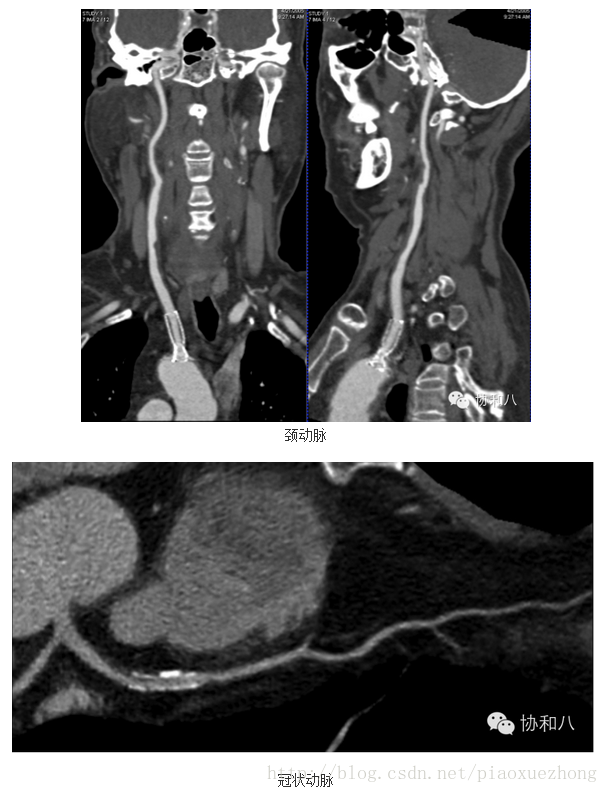

曲面重建技术(CPR)

这种重建技术是在一个维度上选择特定的曲线路径,将该路径上得所有体素在同一平面上进行显示,可以一次评价曲度较大的结构如脾动脉、胰管、冠状动脉等管状结构的全长情况:

胰管

CPR可以观察管腔结构的腔壁病变(如斑块、狭窄等),也可以观察管状结构与周围结构的位置关系,但CPR所显示的不是正常的解剖结构和关系(它是把管状结构拉直了看),同时需要多个角度曲面重建以完整评价病变。